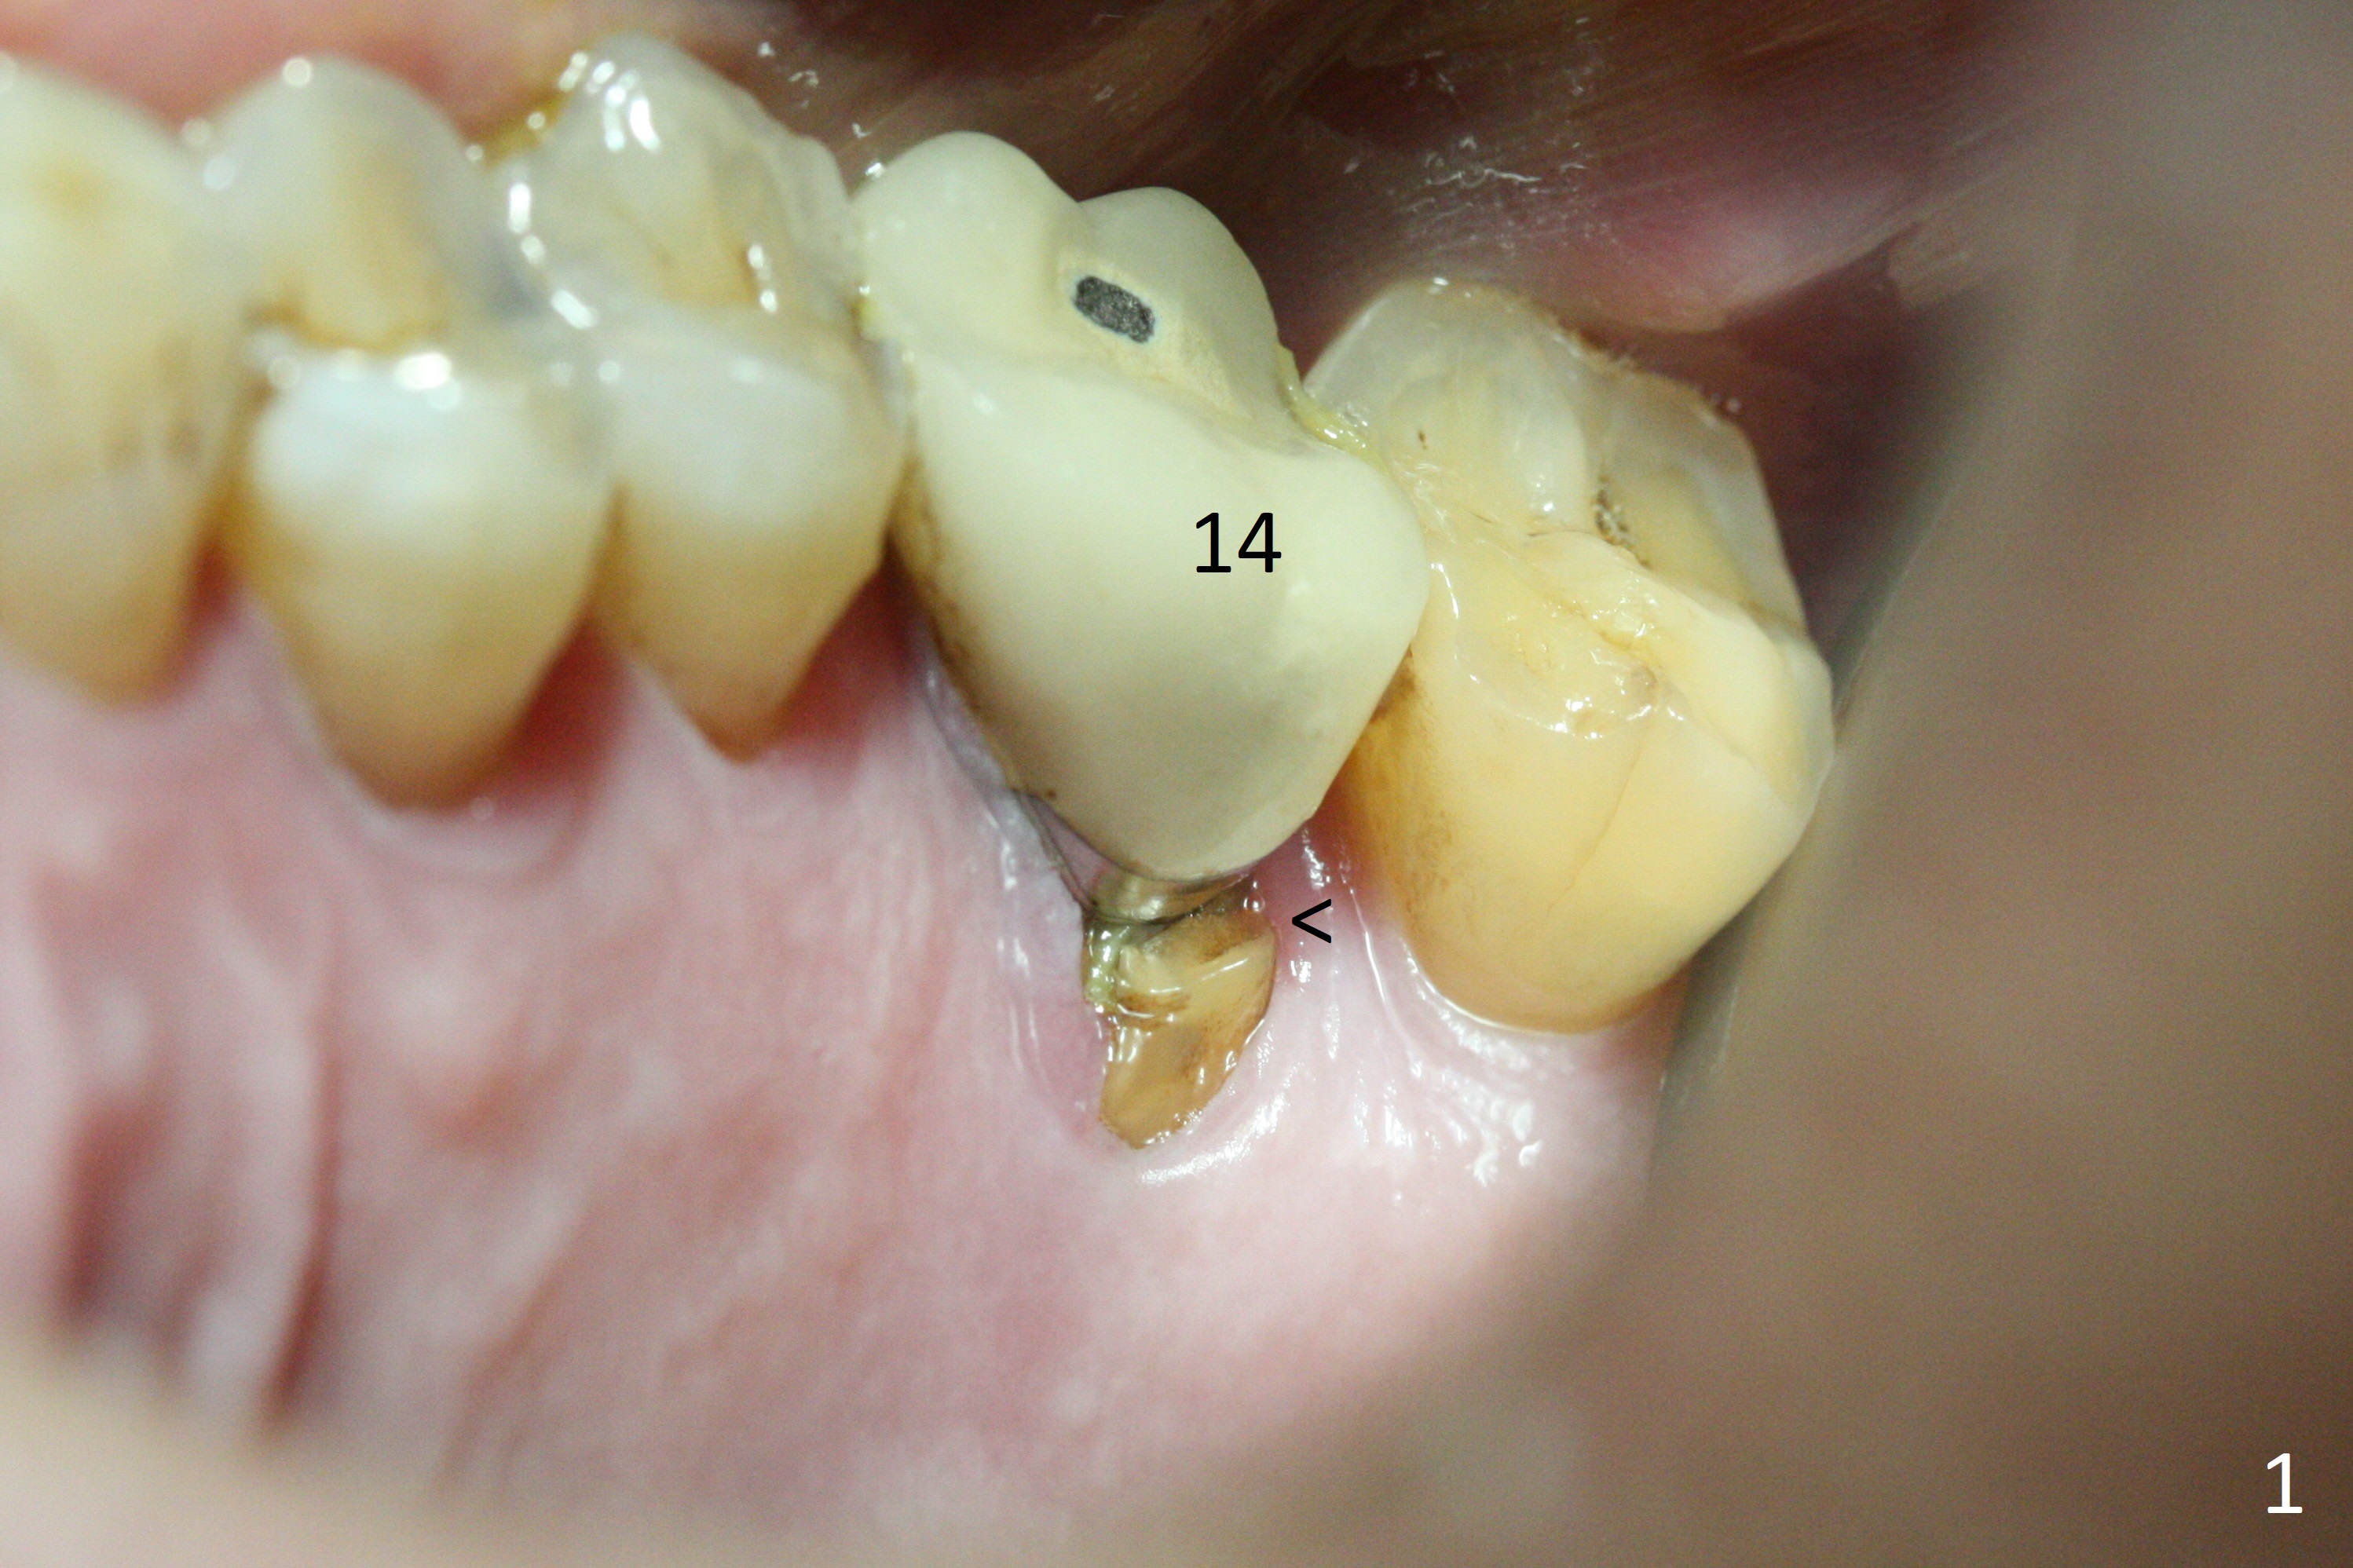

After extraction of the tooth #14 with palatal root fracture (Fig.1 <), sinus membrane perforation is found in the buccal wall of the palatal socket (Fig.2 ^). Osteotomy is initiated in the buccal strut of the septum (Fig.3 *). As the osteotomy increases in diameter, it slides into the mesiobuccal socket (Fig.4). A 5x9 mm implant is placed slightly mesial; after placement of a 6.5x4(2) mm abutment and insertion of collagen plug in the palatal socket, Vera graft is placed in the remaining socket space (Fig.5 *). Nasal hemorrhage persists 1.5 months postop (Fig.6). The distal gingiva is slightly tender and erythematous; a 6x4 mm healing abutment is placed 2.5 months postop (Fig.7,8). Impression is taken after laser gingivectomy 3.5 months postop. The patient feels discomfort at the site 7 days post impression, although the gingiva heals after laser treatment. Two weeks after cementation, the mesial gingiva is mildly tender and the abutment screw is loose. A 6x3 mm healing abutment is placed. The abutment/crown is reseated 10 months postop (Fig.9).